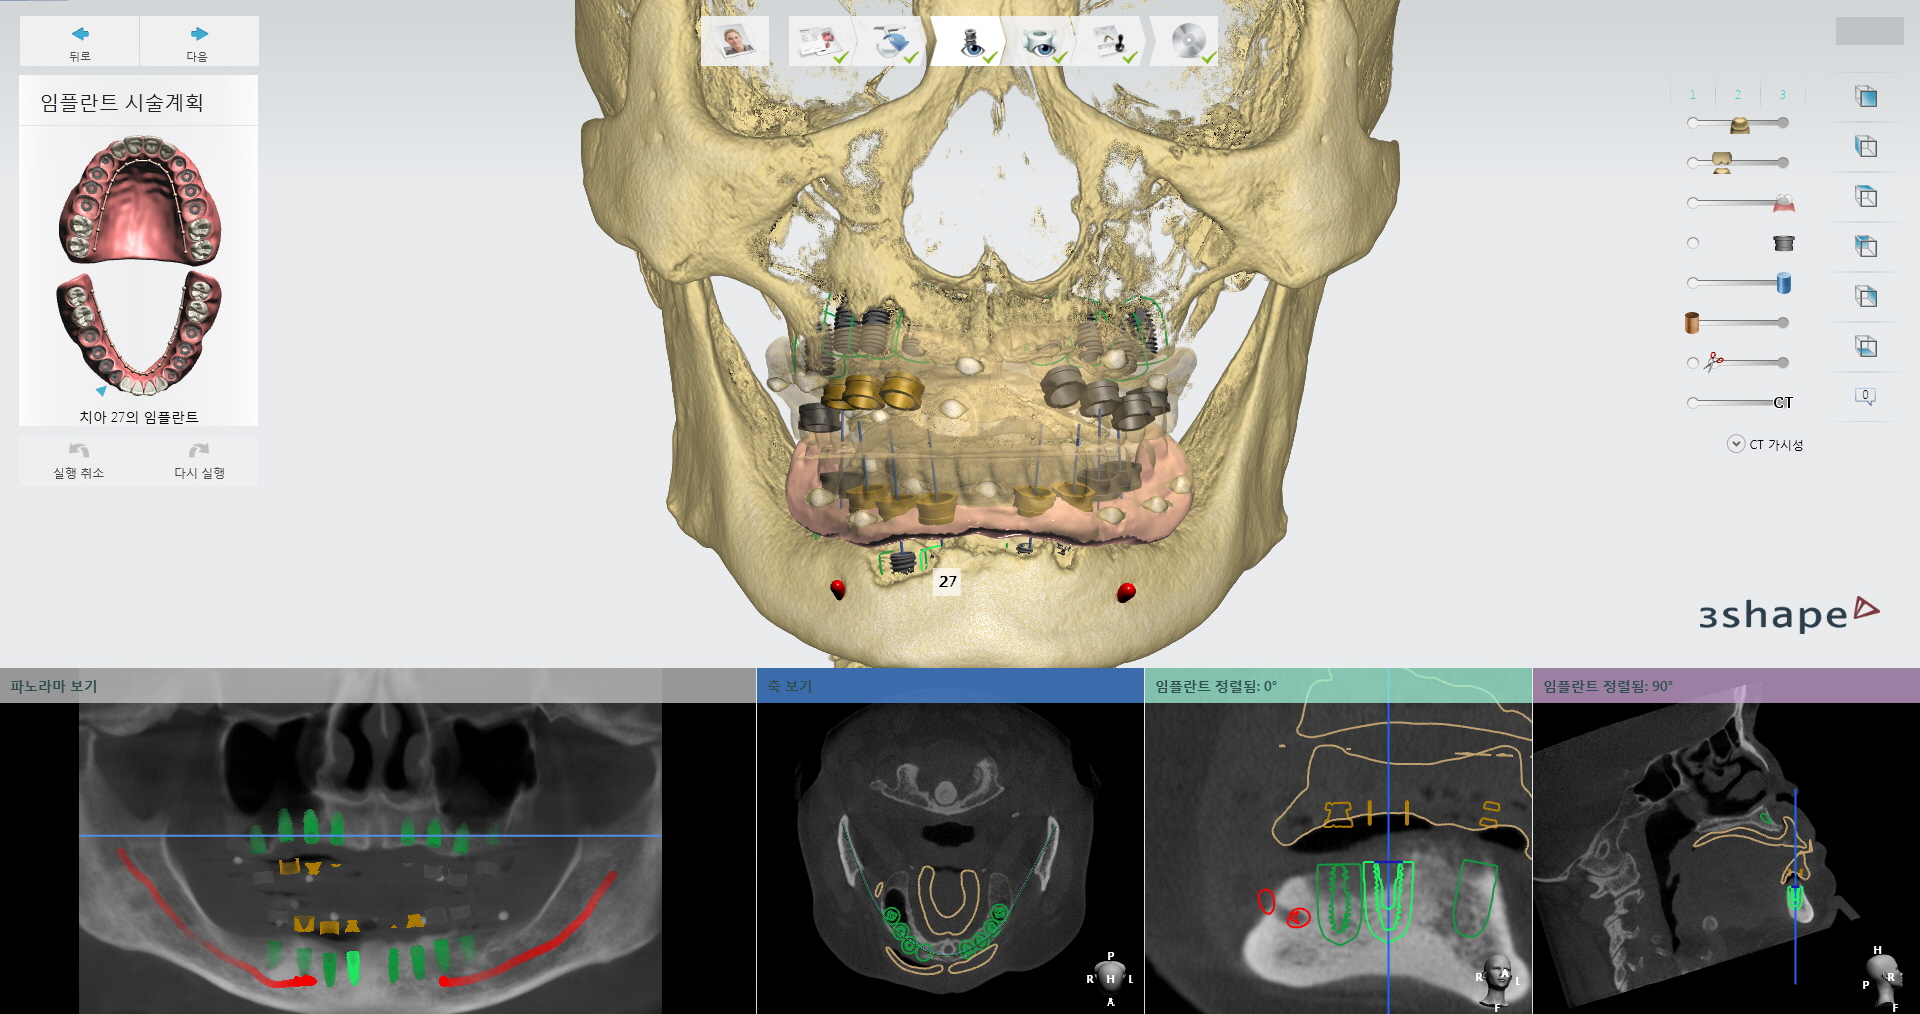

그중 선병원재단(이사장 선두훈) 선치과병원(원장 선경훈)은 세계적 기술력 보유를 목표로 지난 2013년부터 각종 첨단 장비를 설치 및 도입하면서 임플란트 진료시스템을 지속적으로 강화하고 있다. 먼저 임플란트 전 검사 단계에서는 3D 구강스캐너와 치과CT(Cone Beam CT)로 환자의 구강 상태를 정밀하게 진단한다.

구강구조와 턱뼈는 물론, 피부 밑 신경의 상태까지 확인할 수 있다. 뼈와 신경선에 대한 파악은 임플란트와 악안면수술의 성공률을 크게 좌우한다. 골밀도가 낮은 곳에 임플란트를 심거나 신경선을 잘못 건드리면 수술이 실패하거나 신경손상 같은 부작용이 발생할 수 있기 때문이다.

위의 장비들을 통해 얻은 3차원 정보는 즉시 컴퓨터로 전송돼 모의수술 단계를 거친다. 수술을 가장 안전하고 성공적으로 마칠 수 있는 방법을 찾아내는 것이다. 특히 이 모의수술 단계에선 최종보철물이 제작된다. 최종보철물이 바로 제작되는 덕분에 임플란트 식립 기간이 6개월에서 1일로 크게 줄었다. 예전에는 임시치아를 수술 당일에 끼우고 수개월 뒤 다시 내원해 최종보철물로 교체했다. 과거 진료 기간 연장의 주범이었던 아날로그 방식은 선치과병원에서 찾아볼 수 없다.